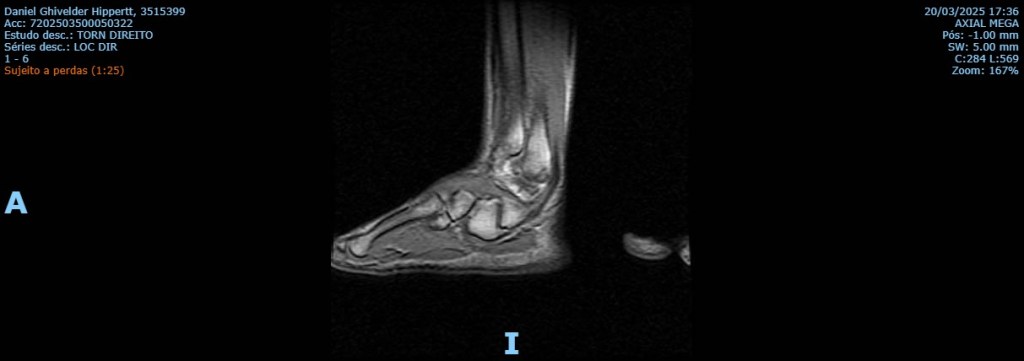

Eu rompi parcialmente um ligamento no tornozelo direito.

Você pode pensar rapidamente: mas Daniel, por que uma lesãozinha no pé te privou de escrever sentado, em um teclado, com os dedos e com a mente que seguem intocados pelo exame de imagem?

Nem o ligamento teve competência para romper-se por completo.